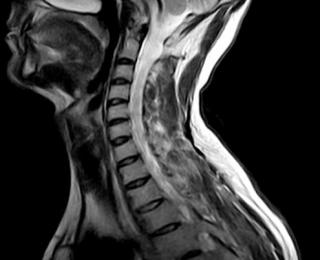

4. МРТ при остеохондроме позвоночника:

• Т1-ВИ:

о Гиперинтенсивность центральной зоны (костного мозга), окруженная гипоинтенсивным кортикальным слоем

о Гипо-/изоинтенсивный хрящевой колпачок, образованный гиалиновым хрящом

• Т2-ВИ:

о Изо- или гипоинтенсивность центральной зоны (костного мозга), окруженная гипоинтенсивным кортикальным слоем

о Гиперинтенсивный хрящевой колпачок, образованный гиалиновым хрящом

• Т1-ВИ с КУ:

о Может отмечаться периферическое усиление и усиление сигнала перегородок в хрящевом колпачке

о МРТ позволяет оценить размеры хрящевого колпачка, состояние смежных нервных и костно-мышечных структур

(Слева) Аксиальный срез, Т1-ВИ: костномозговое пространство остеохондромы, расположенное в просвете спинномозгового канала, с преимущественно гипоинтенсивным хрящевым колпачком, вызывающим стеноз шейного отдела позвоночника и сдавление спинного мозга.